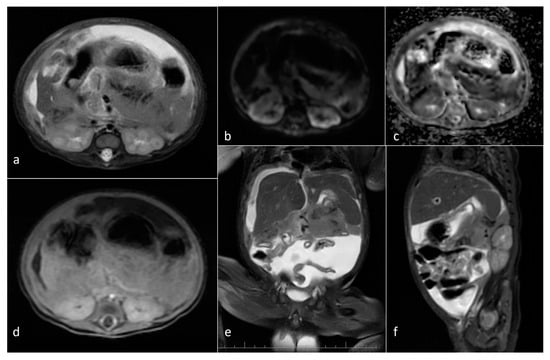

| Neuroblastoma | adrenal gland/infrarenal space | 5 | 11.9 [2.6–24.2] | yes (3/5) (754–1200) | solid/mixed | yes (2/5) | yes (3/3) |

| Mesoblastic nephroma | kidney | 2 | 98.4 [42.9–153.9] | yes (1100–1310) | Solid | 0/2 | yes (1/2) |

| Wilms tumor | kidney | 1 | 366.9 | yes (548) | Mixed | N/A | yes (solid part) |